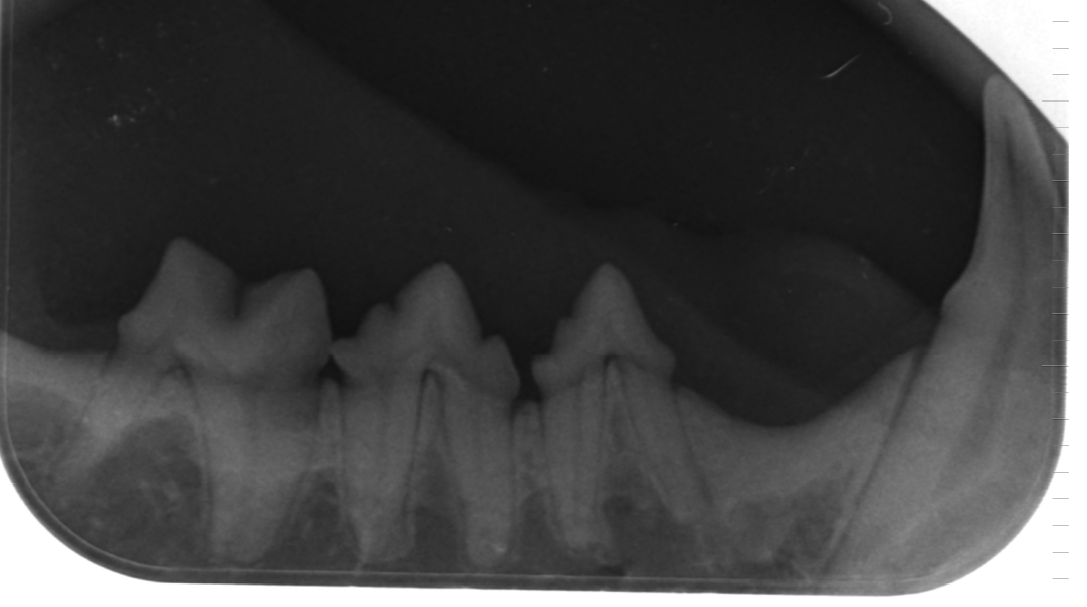

Since 2001, we have been equipped with a digital X-ray unit for all cases of doubt, which enables particularly fine pictures with high transparency. These X-ray images are significantly better in their informative value than normal X-rays and thus often save the preparation of a computed tomography (CT). Conventional X-rays can also be taken by digitization in the data processing. In this form you can send them by e-mail. Since 2019 we do also offer x-rays with a digital Tooth X-Ray. This facilitates and accelerates the collaboration with consulting colleagues as well as the transmission of information during referrals, even over long distances.

Digital dental X-ray.